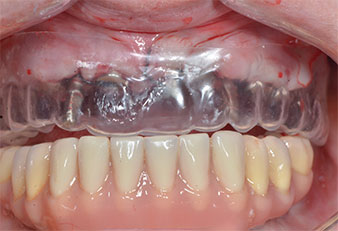

Due to the relatively hard bone (D2) in this area, the 10 mm long implant sites at positions 11 and 21 were finalized with a 4 mm diameter rotary drill, in combination with a W&H WS-75 L surgical contra-angle handpiece, the W&H Implantmed implant motor and the optional W&H Osstell ISQ module. In contrast, due to the soft bone the posterior sites were prepared to a final 3 mm diameter using the Piezomed I3P instrument. The implants were finally placed transgingivally to osseointegrate for three months (Figs. 6-10). The existing denture was retained on four provisional implants (Fig. 8).

Plastic template

Fig. 9: A plastic template reveals sufficient space for the existing prosthesis to serve as a temporary retained on the provisional implants.